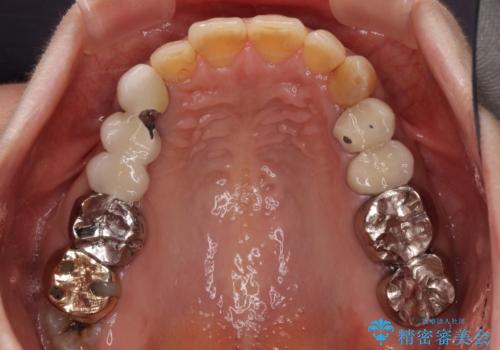

インプラントや歯周外科処置を用いた奥歯の補綴治療

- 下顎の左右奥歯が痛みがあり、噛めないとのことで来院された患者様です。

左右ともに歯根が破折しており、抜歯が必要であったため、抜歯後にインプラント補綴治療を行うこととしました。

左側は骨欠損が著しいことが予想されるため、骨造成術並びに歯肉移植術を併用することとしました。

左上は当初治療予定ではありませんでしたが、クラウンの周りに汚れがたまっていることが気になってきたため、追加して治療を行うこととしました。

歯肉縁下にまで虫歯が及んでいたため、歯冠長延長術を行い、清掃性の改善を試みます。